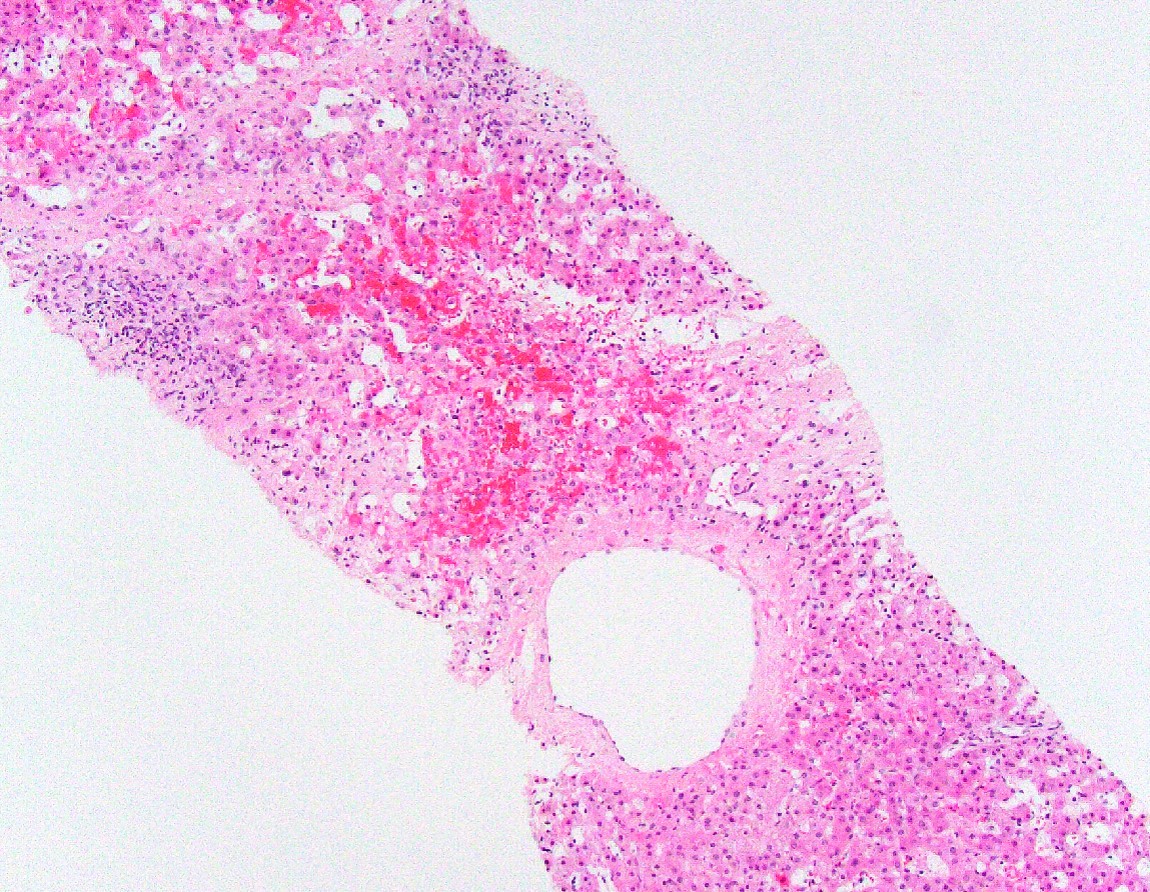

Disease Processes & Lesion Recognition

Examine each slide systematically — architecture first, then cellular detail — before reading the annotated lesson notes.